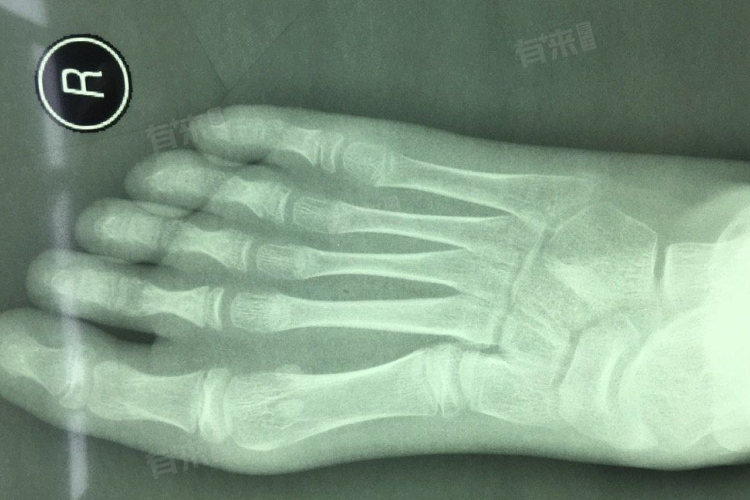

- 如果是拍摄四肢的简单X光片,如手部、脚部等,价格相对较低,一般在100-150元,因为这些部位骨骼结构相对简单,拍摄难度较小。而对于脊柱、骨盆等部位的X光片,由于其结构复杂且重要,价格可能会在150-250元。这些部位的拍摄需要更精确的定位和技术,而且影像对于诊断的要求也更高。